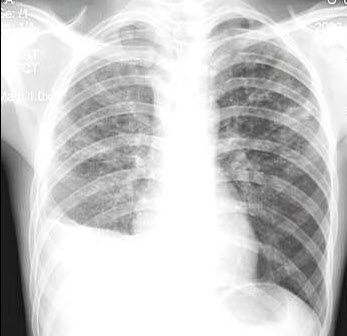

40、单项选择题

女,67岁,咳嗽1周,有甲状腺癌史,结合胸片,最可能的诊断()

A.甲状腺癌肺转移

B.粟粒型肺结核

C.尘肺

D.结节病

E.肺炎